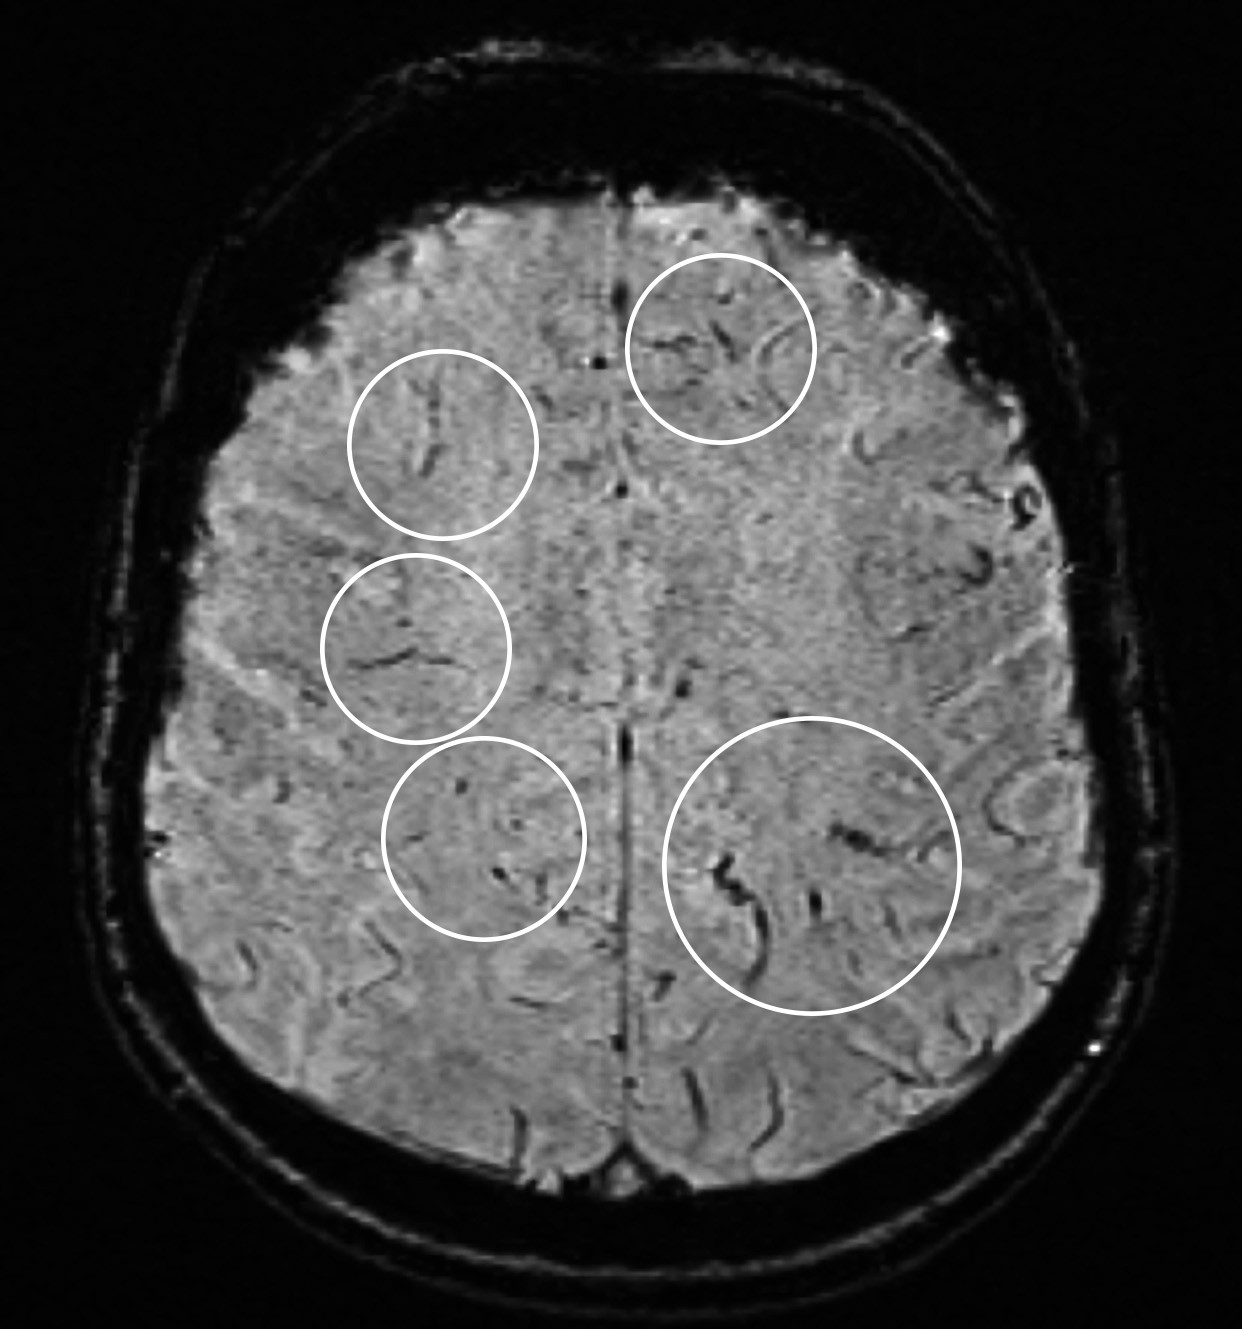

På MR-bildet sees mikroblødninger langs penetrerende kar i hjernen, tolket som cerebral sarkoid mikroangiopati. Susceptibilitetsvektede MR-bilder (susceptibility weighted imaging, SWI) er spesielt følsomme for blodprodukter.

Pasienten ble innlagt grunnet hodepine og dobbeltsyn. MR-bilder viste kontrastoppladning i leptomeninger og okulomotoriusnerver samt fortykket hypofysestilk, som ofte sees ved nevrosarkoidose. Analyse av cerebrospinalvæsken viste inflammasjon (forhøyet celletall, protein og IgG/albumin-indeks), og histologisk undersøkelse av mediastinal lymfeknute viste granulomatøs betennelse. Pasienten fikk behandling med prednisolon og metotreksat og ble symptomfri. Etter to år ble behandlingen trappet ned. Pasienten ble da kognitivt endret, og nye MR-bilder viste mikroblødninger (bildet).

Mikroblødninger sees oftest i basalgangliene ved hypertensiv angiopati og kortikalt ved amyloid angiopati. Blødningene hos vår pasient var lokalisert langs penetrerende kar og ble derfor tolket som best forenlig med cerebral sarkoid mikroangiopati. Behandling ble gjenopptatt og medførte tydelig symptombedring, som nå har vart fire måneder.